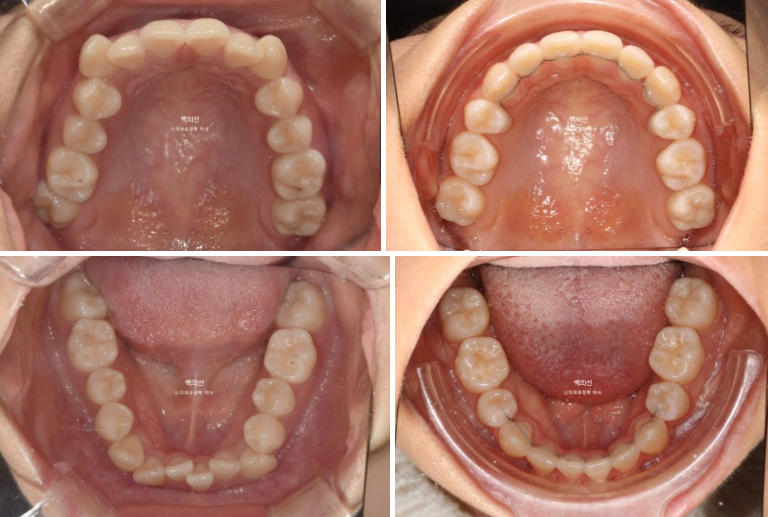

치료시작 6개월째 모습입니다.

상대적으로 하악 보다 상악이 덧니가 심해 상악을 먼저 붙여서 4개월 정도 덧니배열을 먼저 한 후 하악을 나중에 붙였습니다 브라켓 장치 붙이는 시간을 최소화 해야 환자분이 편합니다.

치료 기간 내내 앞니가 뒤로 들어가는 것을 최소화 하고자 발치공간으로 어금니를 하나씩 앞으로 당겨오는 치료를 했습니다.

중심선은 잘 맞습니다.

어금니 교합 관계는 1급이고 물샐틈 없네요